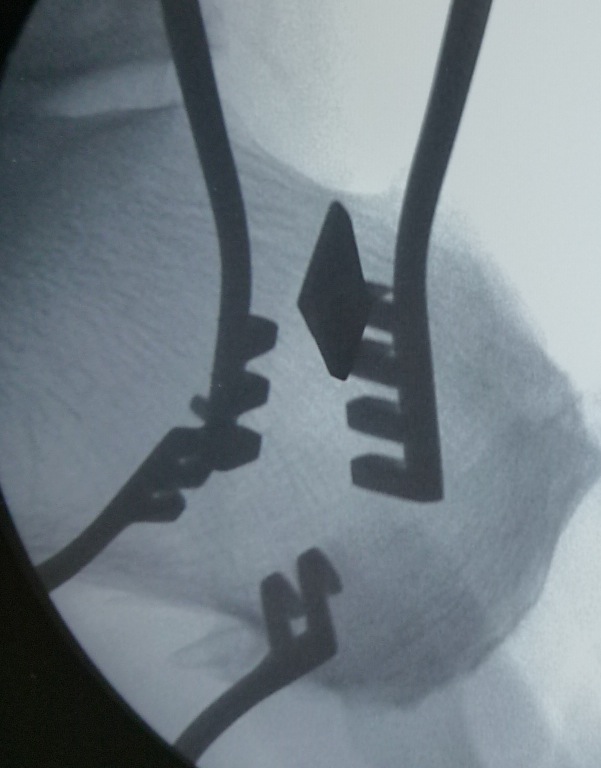

This technique also works well with an osteotome. For example, prior to making a calcaneal osteotomy, I will take the osteotomy, gently tap it in at the bone and then take a bull’s eye view. This will tell me exactly where I am on the bone to make sure I am not too close to the subtalar joint and that the obliquity is good.

Additionally, we can employ the fluoroscopy trick I mentioned above. Once you make your oblique skin incision on the lateral heel and dissect down to the periosteum of the calcaneus, use a Weitlaner retractor or two. Now use fluoroscopy to get a ballpark reading of where the osteotomy will be located. Based on that, you can take an osteotome and gently tap into the bone either proximal or distal to the center to make sure your osteotomy will be exactly where you want it (see right photo).